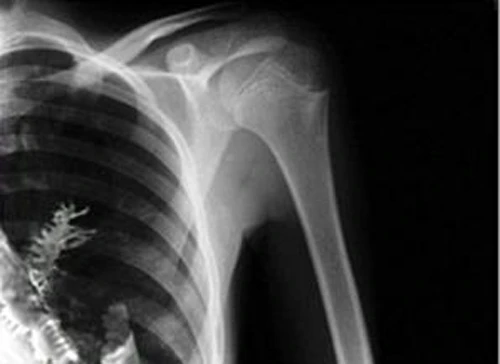

Tháng 5/2010, ông Ron Sveden, 75 tuổi, ở bang Massachusetts, Mỹ, đến bệnh viện với nghi ngờ mắc ung thư phổi. Các bác sĩ chụp X-quang cho ông và phát hiện một hạt đậu đang nảy mầm dài đến 1,25 cm trong phổi.

Theo các bác sĩ, có lẽ bệnh nhân đã ăn đậu, và có một hạt đã "đi lạc đường" xuống phổi, nảy mầm ở đó.